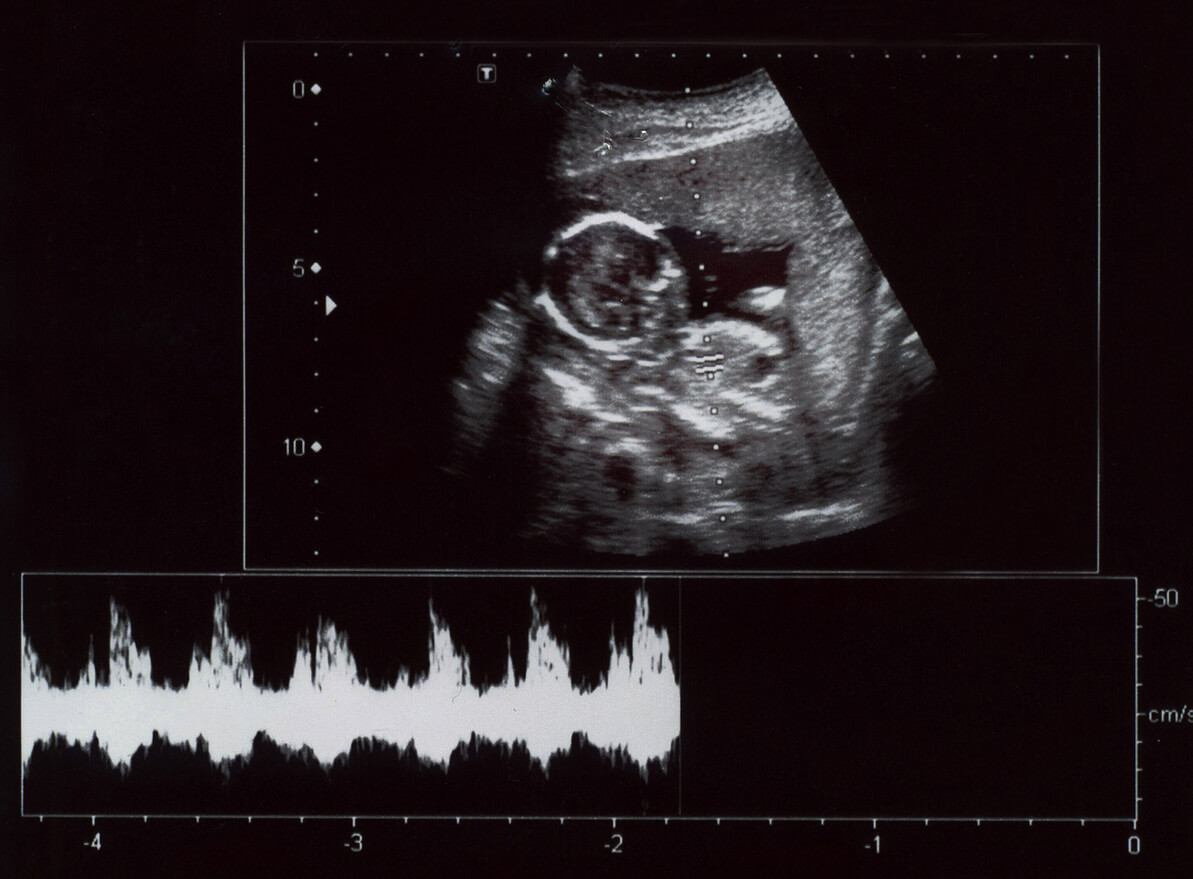

Ultrasonografie, ook wel echografie genoemd, is een diagnostische beeldvormingsmethode waarbij geluidsgolven met een hoge frequentie worden gebruikt om inwendige weefsels te observeren. In het geval van de zwangere vrouw gaat het om het observeren van de groeiende baby.

De verkregen beelden stellen de specialist in staat om de anatomie van de baby en zijn ontwikkeling gedurende de 9 maanden te zien, evenals andere structuren zoals de placenta en het vruchtwater. Op deze manier kunnen eventuele complicaties tijdig worden gediagnosticeerd.

- Doppler-echografie: de kleurendoppler wordt over het algemeen gebruikt voor onderzoeken van de bloedsomloop in aderen en slagaders, omdat vloeistoffen in beweging zichtbaar kunnen worden gemaakt. Gepulseerde Doppler daarentegen bestudeert bloedvaten en het hart.